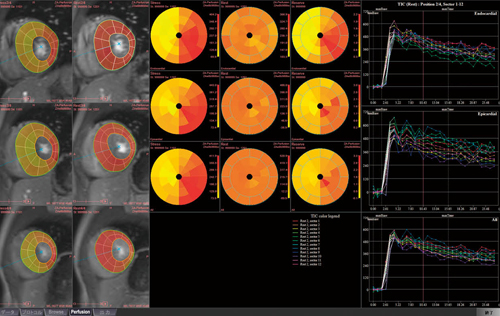

MRパフュージョン解析結果画面(ziostation2)

左:心筋画像上に血流量をカラー化したものを重ね合わせて表示

中央:安静・負荷時の心筋血流量と冠血流予備能をbull's eye map表示

右:心筋血流信号の経時変化をグラフ化して表示